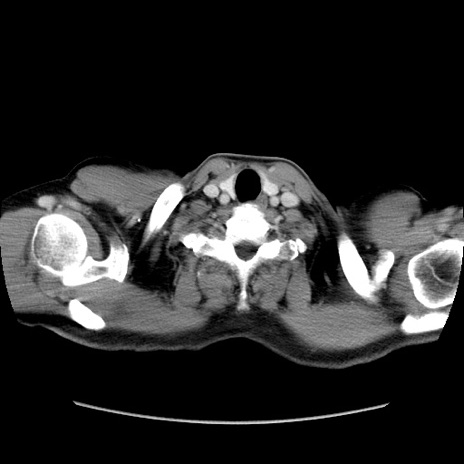

症例34(横断像)

【症例】60歳代 男性

【主訴】右鼠径部膨隆

【現病歴】1年程前より右鼠径部膨隆あり。自己にて還納可能だったため放置していた。3時間前より右鼠径部の脱出を認め、還納困難となり受診。

【既往歴】高血圧

【身体所見】右鼠径部に小児頭大の膨隆あり。弾性硬であり、用手還納は困難。左鼠径部にも膨隆を認める。脱出はなし。

【データ】WBC 15500、CRP 測定なし